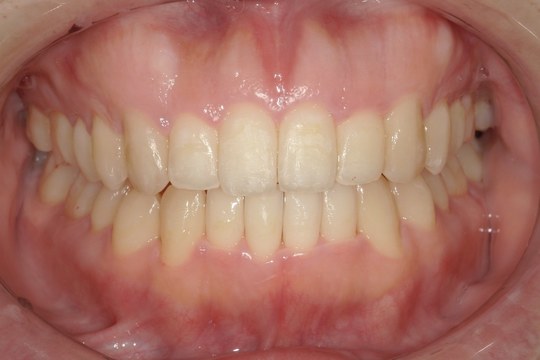

Y.S. 30代男性

全体的にガタガタしているのが気になるという主訴だったため、上下左右第一小臼歯を抜歯し、叢生を並べました。

治療の期間:R3. 9/1〜R5. 10/31

治療の価格:88万円